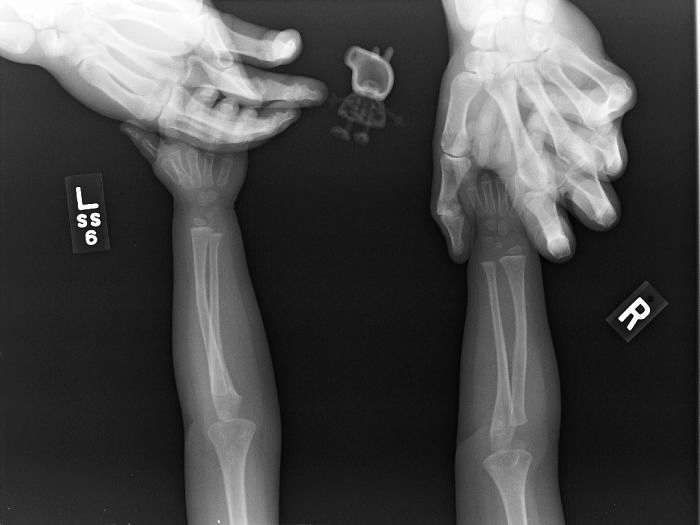

Стандартный снимок молочных зубов детей 6-12 лет